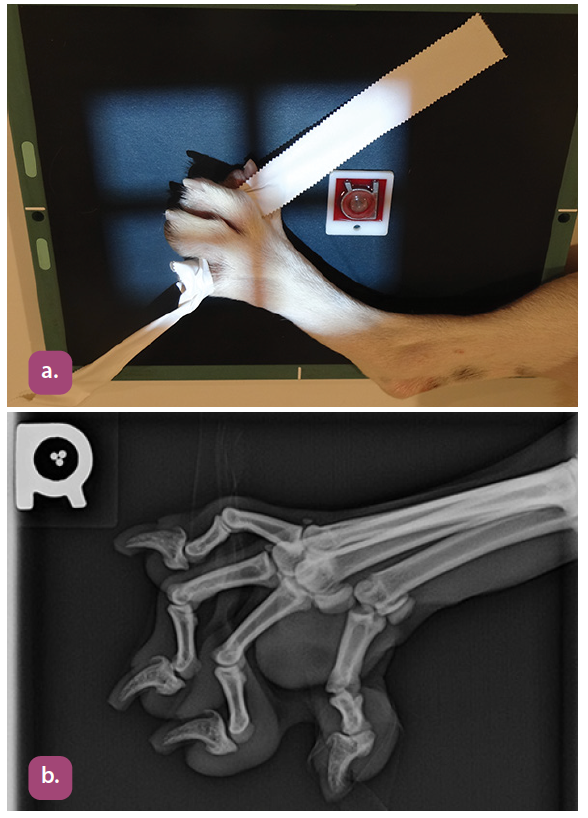

lateral projection of the digits

mediolateral projection of the metacarpus

mediolateral projection of the phalanges